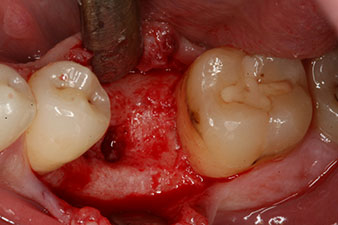

However, six weeks after the extraction incomplete ossification was found after preparation of the mucoperiosteal flap in the region of the former mesial alveolus.

The implant was placed as planned after thorough removal of the granulation tissue (blueSky, bredent).

The torque used for the machine-driven placement was 43 Ncm. In addition, after screwing a measuring post (SmartPeg) specially matched to the implant, the ISQ value was measured with the probe of the W&H Osstell ISQ module.

This module is an optional extra for the W&H Implantmed and is docked to the implantology motor (see Fig. 11). The dimensionless ISQ value immediately after insertion was 64 orovestibular and 68 mesiodistal (maximum value = 100).

These values could have indicated open healing or even immediate restoration. Due to the insufficient crestal bone volume at the implant, the region was augmented with the bone chips collected during preparation of the implant bed and sutured to exclude saliva.